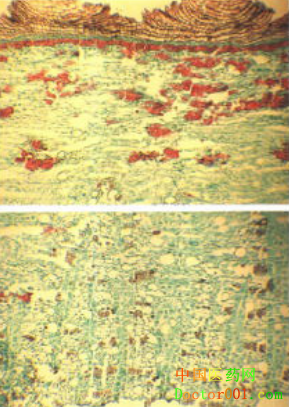

【標題】 厚樸 【拼音】 Houpo 【概述】 為木蘭科植物厚樸Magnolia officinalis Rehd.et Wils.或凹葉厚樸M. O. R.et Wils.Var. biloba Rehd. et Wils.的干燥干皮、根皮及枝皮。主產于四川、湖北等地。4~6月剝取,根皮及枝皮直接陰干,干皮置沸水中微煮后堆置陰濕處,“發汗”至內表面變紫褐色或棕褐色時,蒸軟取出,卷成筒狀,干燥。切絲,姜制用。 【性味歸經】 苦、辛,溫。歸脾、胃、肺、大腸經。 【功效】 燥濕消痰,下氣除滿。 【應用】 1.濕阻中焦,脘腹脹滿。本品苦燥辛散,能燥濕,又下氣除脹滿,為消除脹滿的要藥。常與蒼術、陳皮等同用,如平胃散(《和劑局方》)。 2.食積氣滯,腹脹便秘。本品可下氣寬中,消積導滯。常與大黃、枳實同用,如厚樸三物湯(《金匱要略》)。若熱結便秘者,配大黃、芒硝、枳實,以達峻下熱結,消積導滯之效,即大承氣湯(《傷寒論》)。 3.痰飲喘咳。本品能燥濕消痰,下氣平喘。若痰飲阻肺,肺氣不降,咳喘胸悶者,可與蘇子、陳皮、半夏等同用,如蘇子降氣湯(《和劑局方》)。若寒飲化熱,胸悶氣喘,喉間痰聲漉漉,煩躁不安者,與麻黃、石膏、杏仁等同用,如厚樸麻黃湯(《金匱要略》)。若宿有喘病,因外感風寒而發者,可與桂枝、杏仁等同用,如桂枝和厚樸杏子湯(《傷寒論》)。 此外,七情郁結,痰氣互阻,咽中如有物阻,咽之不下,吐之不出的梅核氣證,亦可取本品燥濕消痰,下氣寬中之效,配伍半夏、茯苓、蘇葉、生姜等藥,如半夏厚樸湯(《金匱要略》)。 【注意】 本品辛苦溫燥濕,易耗氣傷津,故氣虛津虧者及孕婦當慎用。 【用法用量】 煎服,3~10g。或入丸、散。 【成藥】 厚樸花 【臨床研究】 1.化學成分:含揮發油約1%,油中主要含β-桉油醇和厚樸酚。此外,還含有少量的木蘭箭毒堿、厚樸堿及鞣質等。 2.藥理作用:厚樸煎劑對肺炎球菌、白喉桿菌、溶血性鏈球菌、枯草桿菌、志賀氏及施氏痢疾桿菌、金黃色葡萄球菌、炭疽桿菌及若干皮膚真菌均有抑制作用。厚樸堿、異厚樸酚有明顯的中樞性肌肉松弛作用。厚樸堿、木蘭箭毒堿能松弛橫紋肌。對腸管,小劑量出現興奮,大劑量則為抑制。厚樸酚對實驗性胃潰瘍有防治作用。厚樸有降壓作用,降壓時反射性地引起呼吸興奮,心率增加。 3.臨床研究: 據報道,以厚樸為主或適當配伍還可用于治療其它多種疾病,如:厚樸35g,枳實30g,大黃20g,治療腸梗阻130例,有效率85.3%(中醫藥學報,1989,5:39);用厚樸9-15g,加水分煎2次,頓服,治療肌強直,療效較好(中醫雜志,1985,6:419);用厚樸、枳實、大黃、芒硝(沖)各9g,行X線快速腸道造影,診斷右側結腸癌10例,效果顯著(上海中醫藥雜志,1983,4:21);另可用厚樸預防術后腸粘連及閉經癥。 【參考文獻】 1.《神農本草經》:“主中風傷寒,頭痛,寒熱,驚悸,氣血痹,死肌,去三蟲。” 2.《名醫別錄》:“主溫中,益氣,消痰下氣,治霍亂及腹痛,脹滿,胃中冷逆,胸中嘔逆不止,泄痢,淋露,除驚,去留熱,止煩滿,厚腸胃。” 3.《本草綱目》引王好古語:“主肺氣脹滿,膨而喘咳。” 【圖片】 凹葉厚樸 ![]() 厚樸 厚樸《常用中藥》 ![]() 厚樸《本草圖苑》 ![]() 厚樸《本草綱目》 ![]() 藥材厚樸橫切面 ![]() 藥材厚樸橫切面(凹葉厚樸) ![]() 藥材厚樸(干皮) ![]() 藥材厚樸(枝皮) ![]() 藥材厚樸(根皮) ![]() 【表格】 厚樸《中藥歌決》 【歌決】 厚樸苦辛藥性溫,能歸脾胃肺大腸; 降氣除滿化食積,健胃整腸止瀉良; 胃寒腹痛下痢嘔,霍亂吐瀉胸悶脹。 (責任編輯:Doctor001) |